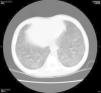

Tras transfundirle un concentrado de hematíes se trasladó a nuestro centro para completar estudio. A su llegada presentaba fiebre y dificultad respiratoria con hipoxemia precisando oxigenoterapia de alto flujo y transfusión de un segundo concentrado de hematíes (15 ml/kg) por Hb 6,7 g/dl en control analítico. En la radiografía de tórax (fig. 1) se visualizó una imagen compatible con edema agudo de pulmón. El paciente fue ingresado en la unidad de cuidados intensivos donde se llevó a cabo restricción de líquidos, tratamiento diurético (furosemida) y soporte respiratorio con ventilación no invasiva produciéndose una mejoría progresiva tanto clínica como radiológica. Durante el ingreso, con objeto de realizar el diagnóstico etiológico del cuadro de anemia aguda, se estudió el metabolismo del hierro que fue normal excepto una transferrina ligeramente disminuida de 187 mg/dl, estudio de anemias hemolíticas (Coombs directo negativo y determinación de glucosa 6-P-deshidrogenasa de 30 U/1012 RBC –[valores normales 146-376 U/1012 RBC]), estudio de hemoglobinopatías con una Hb S 20% y hemorragia oculta en heces negativa. Recibió al alta los diagnósticos de déficit de G6PD y estado de portador de drepanocitosis, sin que estos hallazgos justificasen claramente los episodios de anemia.